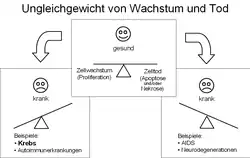

In einem gesunden Organismus werden die Zelltypen, aus denen sich die verschiedenen Gewebe der Organe aufbauen, in einem ausgewogenen artspezifischen Gleichgewicht gebildet und regeneriert, was als Homöostase bezeichnet wird. In diesem Zustand der Homöostase gibt es ein Gleichgewicht zwischen der Vermehrung von Zellen (Zellproliferation) und dem Zelltod. Der Hauptanteil des Absterbens von Zellen erfolgt dabei durch Apoptose, bei der die Zellen „Selbstmord“ begehen. In pathologischen Situationen kann dieses Absterben auch durch Nekrose geschehen. Bei Krebs ist dieses Gleichgewicht zugunsten des Zellwachstums verändert. Die Krebszellen wachsen dabei ungehindert, da hemmende Signale nicht erkannt oder nicht ausgeführt werden. Der Grund liegt in Defekten der Erbinformation, die durch Mutationen entstanden sind.

Etwa 5.000 der insgesamt 25.000 Gene des Menschen sind für die sichere Erhaltung der Erbinformation von einer Zellgeneration zur nächsten zuständig. Diese sogenannten Tumorsuppressorgene überwachen die korrekte Abfolge der Basenpaare in der DNA nach jeder Reduplikation, entscheiden über die Notwendigkeit von Reparaturvorgängen, halten den Zellzyklus an, bis die Reparaturen ausgeführt sind, und veranlassen gegebenenfalls einen programmierten Zelltod (Apoptose), falls die Reparatur nicht zum Erfolg führt. Daneben sind die Protoonkogene zuständig für die Einleitung oder den Unterhalt der Proliferation der Zelle und ihrer anschließenden Entwicklung zu einem bestimmten Zelltyp (Differenzierung).

Nach der heute als plausibel geltenden Theorie der Krebsentstehung (Karzinogenese) ist das primäre Krankheitsereignis eine Veränderung in einem dieser Wächtergene – entweder durch einen Kopierfehler oder seltener durch eine angeborene Mutation. Dieses Gen kann dann den von ihm überwachten Teilschritt nicht mehr korrekt begleiten, sodass es in der nächsten Zellgeneration zu weiteren Defekten kommen kann. Ist ein zweites Wächtergen betroffen, so potenziert sich der Effekt fortlaufend. Wenn auch Apoptose-Gene (z. B. p53) betroffen sind, die in einer solchen Situation den programmierten Zelltod auslösen müssten, werden diese Zellen potentiell unsterblich. Durch die Aktivierung der Protoonkogene wird ein Krebs zum Wachstum angeregt, was in einer Raumforderung und in Folge zu auftretenden Schmerzen führen kann. Zur Krebsentstehung sind mehrere solcher Mutationen notwendig (englisch multiple hit model).[20] Hierbei hat sich die Annahme von Peter Nowell bestätigt, dass zur Entstehung eines malignen Tumors mindestens sechs bis sieben Mutationen nötig sind.[21]

Mehrschrittmodell bzw. Dreistufenmodell

Die meisten Krebsforscher gehen vom sogenannten ‚Mehrschrittmodell‘ der Krebsentstehung aus. Das Mehrschrittmodell versucht die Krebsentwicklung ursächlich zu verstehen. Hierbei entspricht jeder einzelne Schritt einer bestimmten genetischen Veränderung. Jede dieser Mutationen wiederum treibt die stufenweise fortschreitende Verwandlung einer einzelnen normalen Zelle in hochmaligne Abkömmlinge voran (Maligne Transformation).[27] Die eigentliche Malignität (Bösartigkeit) der entarteten Zelle wird in der Phase der Progression erreicht. Die Begriffe Promotion und Progression werden zunehmend vom Begriff der Co-Karzinogenese ersetzt.

Das ältere sogenannte ‚Dreistufenmodell‘ gliedert die Krebsentstehung dagegen in Phasen: Initiation, Promotion und Progression. So soll die Jahre bzw. Jahrzehnte dauernde Latenzphase zwischen dem initialen DNA-Schaden, also der Transformation einer einzelnen Zelle, und dem nachweisbaren Tumor erklärt werden. Problematisch am Dreistufenmodell ist, dass die Begrifflichkeiten Initiation, Promotion und Progression lediglich beschreiben und nicht die Ursache erklären.